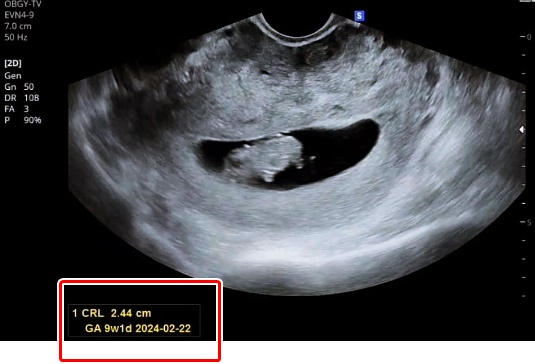

2. GA (Gestational Age): 임신기간, 임신주수

태아의 주수를 뜻하며 Ow Od (O week, O day), 주와 일수로 표기됩니다.

임신 몇 주 며칠인지 알 수 있어요.

4. CRL (Crown Rump Length): 머리부터 엉덩이까지 길이

임신 초기에는 CRL로 태아의 크기(키)를 확인합니다.

임신 중기부터는 머리직경, 복부둘레 등으로 예상 키를 확인하기 때문에 중기부터는 크게 의미를 두지 않는다고 합니다.